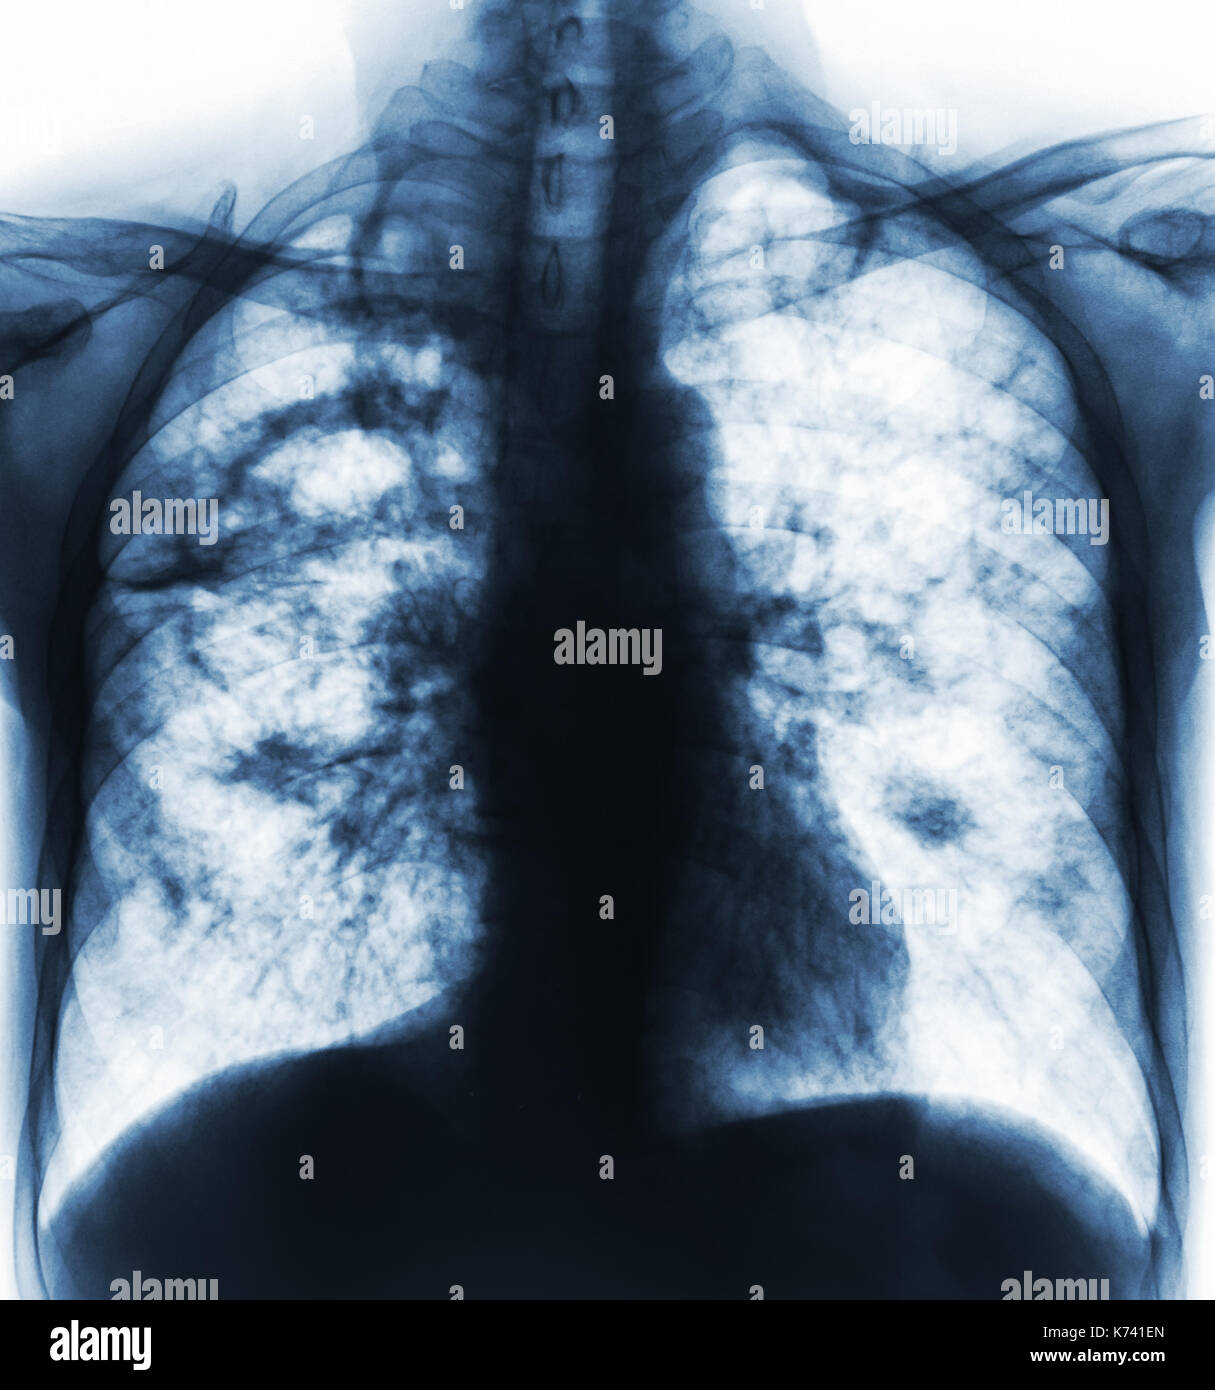

From www.alamy.com

From mavink.com